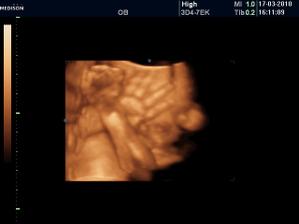

Vyrobene z velkej lasky